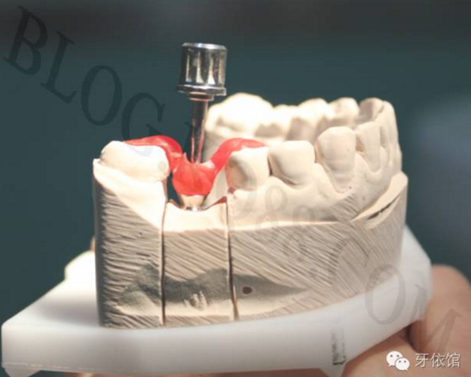

將基臺定位器安裝在模型上的粘結(jié)基臺上,用螺絲刀旋下中央螺絲。

將基臺定位器和基臺同時在口內(nèi)就位,用手旋緊中央螺絲,試戴烤瓷牙,調(diào)整咬合,再用扭矩扳手旋緊中央螺絲。